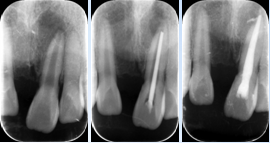

苏琼医师经典案例:

根管垂直加压充填

反复瘘管根管再治疗